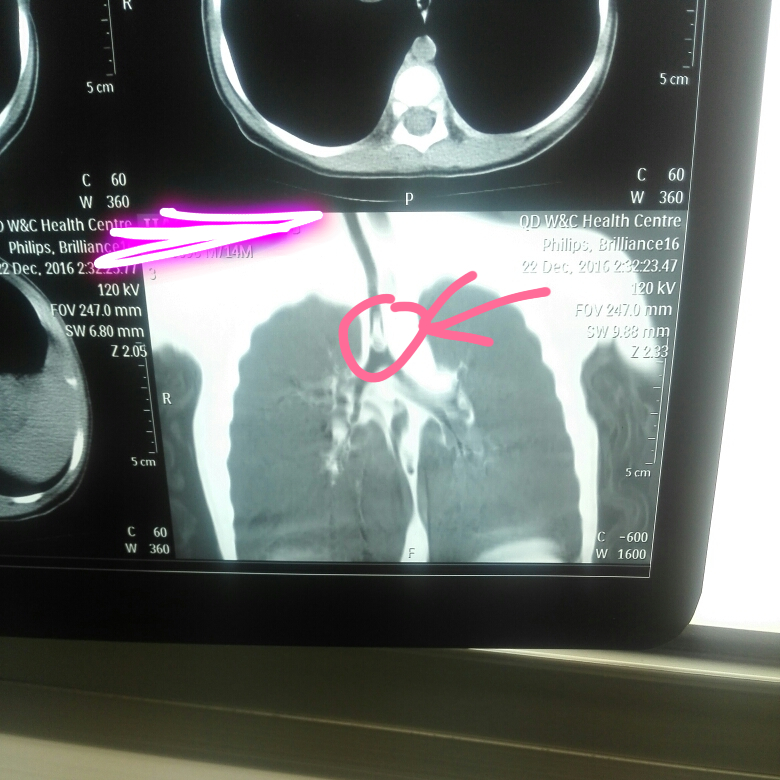

2岁的小明正在吃着核桃仁,突然呛着了,剧烈咳嗽,过一段时间慢慢不大咳了,后来就出现间断性咳嗽,喘息。到医院行CT检查发现一侧支气管堵塞,在全麻下经支气管镜取出一大块核桃仁。这就是气管异物的典型表现。

气管异物一般医生通过有异物吸入病史,再通过X线、CT检查来确诊。